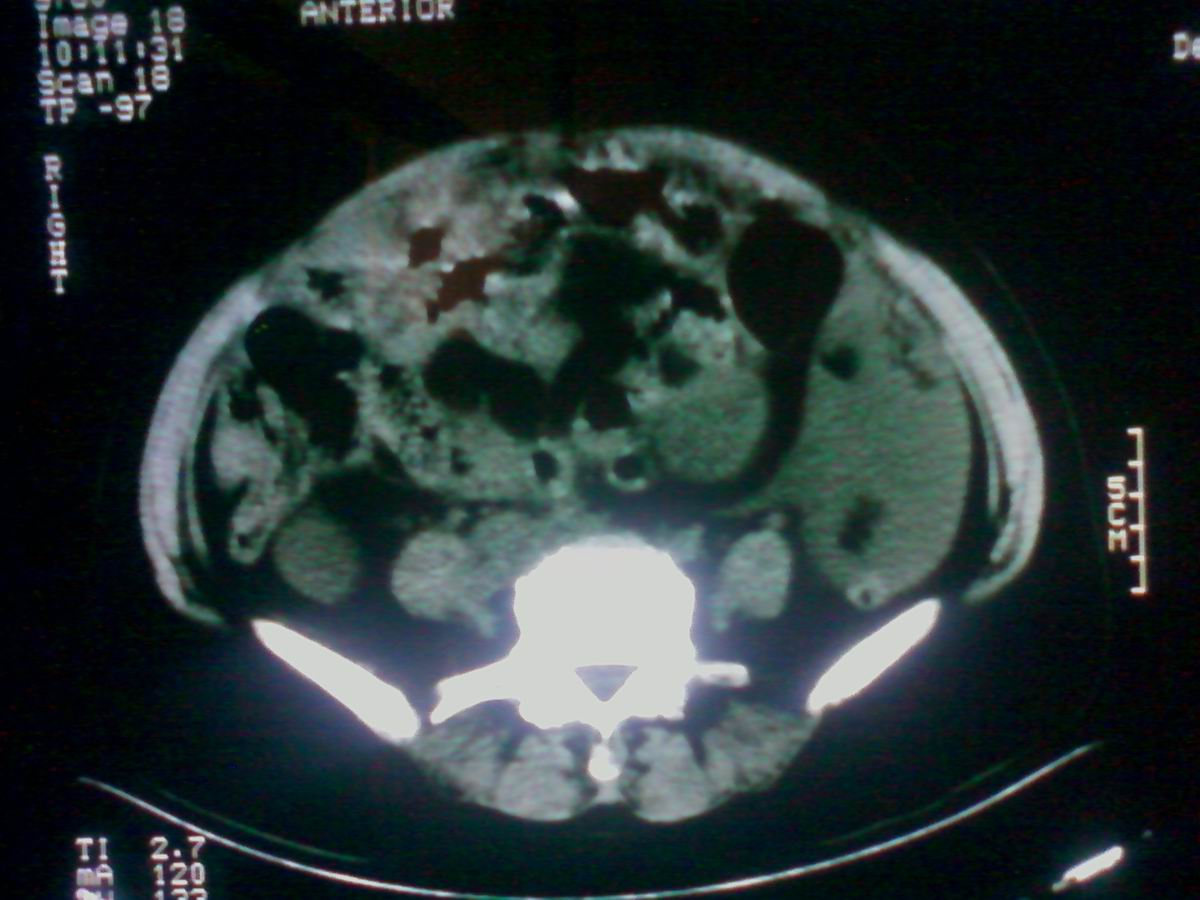

标题: CT25799:女性患者,45岁,腹胀,上腹部疼痛来诊,B超示盆腔 [打印本页]

标题: CT25799:女性患者,45岁,腹胀,上腹部疼痛来诊,B超示盆腔

考虑卵巢癌伴腹水

1)考虑卵巢恶性肿瘤。2)腹水。